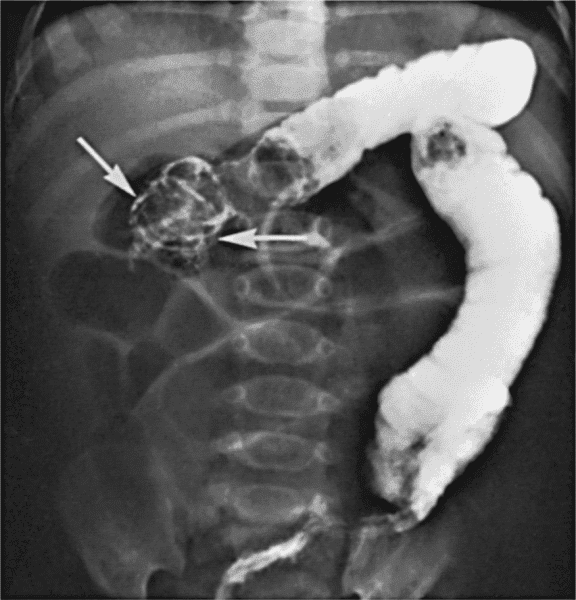

Hirschsprung Hastalığı Nedir? Hirschsprung has­talığı; kalın bağırsaklarda hareket bozukluğu nedeniyle ortaya çıkan tıkanıklıktır. Bu has­talık...